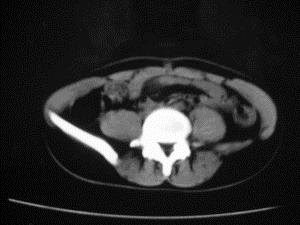

患者女,20岁,被车撞伤3小时,pe:全腹肌紧张,压痛反跳痛,以右上腹为著,肠鸣音减弱。有手术结果。![]() ![]() ![]() ![]() ![]() ![]() ![]() ![]() ![]() ![]() ![]() ![]() ![]() ![]() ![]() ![]() ![]() ![]() ![]() ![]() ![]() jiajie发言: ![]() 考虑空腔脏器穿孔。 dyqct发言:考虑:1、肝左叶外侧段断裂伤伴少量腹血。2、空腔脏器穿孔。 fangzheng发言:仅见腹腔内游离气体,提示空腔脏器穿孔。 guoke发言:胃内密度增高,肠腔内充满气体,考虑肠腔破裂出血 mmg94发言:胃后壁见一增厚软组织密度影,肝左叶前见游离气体影,左腹腔内局部肠管壁、系膜增厚。并见类圆形软组织。以上征象提示消化道管腔破裂,小肠、肠系膜挫裂伤,腹腔血肿形成。 拾荒者发言:肝实质密度不均匀,胃内见不均匀高密度影。考虑:肝挫裂伤,胃内应激性溃疡出血。 守望可可西里发言: 以下是引用jiajie在2006-6-20 15:49:00的发言:[br] [br][br]考虑空腔脏器穿孔。jiajie老师,我鼓起了很大的勇气才决定给您唱个反调儿,如果我错了,请您一定给我指出来,谢谢您了。我反复看了解剖图谱,觉得您所说的“考虑空腔脏器穿孔”上图所用箭头标明的不是游离气体。请您看以下几幅图片: ![]() ![]() ![]() ![]() ![]() ![]() ![]() ![]() 再请您看向医生老师发表的解剖图谱3幅 ![]() ![]() ![]() 这以下几幅图,我认为是肝包膜下积血。不过,说实在话,我没有发现有明显的肝挫裂伤。不对的地方请您一定指出来,再次感谢您了,jiajie 老师! ![]() ![]() ![]() ![]() 这下面几幅图片,我认为有明显的左中上腹部小肠损伤。 ![]() ![]() ![]() ![]() ![]() ![]() ![]() ![]() jiajie 老师,估计我说的是错误的,但我实在闹不明白,请您一定不要笑话我,并指出我的错误,以便于我减少工作中的失误。再次感谢您了,jiajie 老师! 至于胃内的不均匀高密度,我认为拾荒者战友说的有道理,胃内应激性溃疡出血和胃内容物混合所致。 手术结果:左肝叶(iv段)前缘长约8cm挫裂伤口,舌叶根部下< |